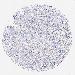

BRCA TCGA BRCA VALIDATION PROTEIN EXPRESSION